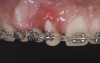

Fig 5. Start of orthodontic forced eruption to develop sites Nos. 6 and 8 before implant placement. A denture tooth was common-tied to the archwire to serve as a pontic. Anchorage requirements determined the extent of bracket placement.

Figure 5

Due to its predictability in achieving bone remodeling and developing alveolar ridge height while preserving or improving soft-tissue architecture, forced eruption was included as part of the interdisciplinary approach to treat the patient in the present case (Figure 5). Only stretching forces are applied to the periodontal ligament during the forced-eruption movement. This provides the stimulus for bone apposition within the socket walls. Generally, the orthodontic movement should be controlled so the root is extruded without impinging on the socket walls. In the presence of periodontal health, bone apposition and gingival remodeling will result in coronal proliferation of the attachment apparatus.29,30

Successful outcomes with forced eruption require the establishment of treatment endpoints, which may include overcompensation beyond the desired soft- and hard-tissue changes. For the present case, achieving ideal gingival-alveolar socket architecture required force-erupting tooth No. 6 to the level of the apical third and tooth No. 8 beyond the confines of its alveolus. As the gingival sulcus is everted through the eruption process, a gingival red patch corresponding to the nonkeratinized sulcular epithelium may appear, as shown around tooth No. 8 in Figure 8 and Figure 9. This tissue will develop into keratinized gingiva when exposed to the oral environment.31,32 Additionally, when forced eruption of this magnitude is performed, there may be a tendency for lingual displacement that needs to be addressed with root-torquing orthodontic auxiliaries (Figure 6 and Figure 7).

When forced eruption is completed, the teeth should be splinted for a 3-month stabilization period,30 which will allow mineralization of osteoid tissue and settling of the gingival remodeling process. The degree of forced eruption in the present case was such that extreme mobility precluded the use of a provisional restoration. Instead, a metal-reinforced direct composite splint extending from teeth Nos. 6 to 8 was fabricated in situ (Figure 8 and Figure 9). When compared with the preoperative condition (Figure 2), Figure 8 and Figure 9 depict the treatment progression with forced eruption. The restoration of adequate alveolar height was achieved while enhancing the soft-tissue architecture, and the everted sulcular epithelium on tooth No. 8 proceeded to develop keratinization. However, the pre-existing defect still manifested itself in the form of a residual cleft.